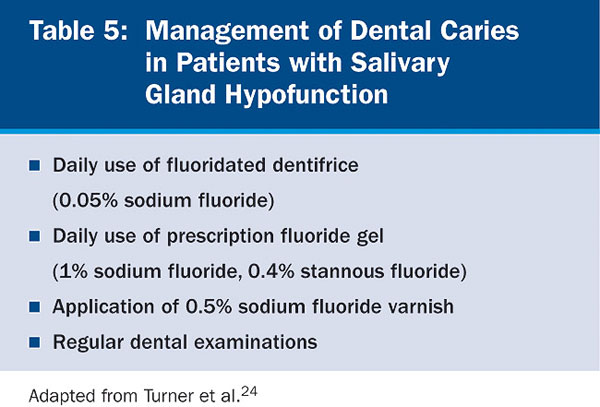

Fluorides, remineralizing solutions, and a noncariogenic diet are critical for preventing dental caries (Table 5). Regular dental examinations should be every 2 to 6 months, based on risk factors and disease susceptibility, such as past caries experience, periodontal status, quantity and quality of saliva, and disabling conditions that prevent oral hygiene maintenance.